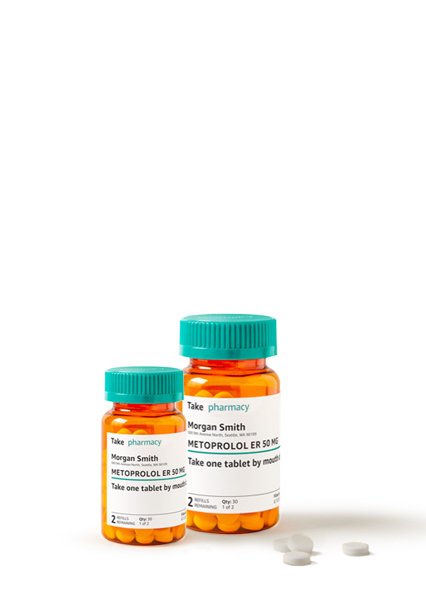

Blood

Pressure

Monitor

Sale Off 30%

Save flat 25% extra on medicines & enjoy FREE delivery with PLUS membership

Order medicines and get same-day delivery. 100% Secure delivery without contacting the courier